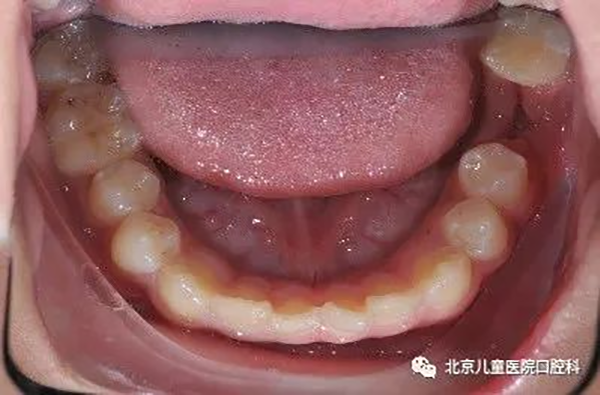

2、前牙严重前突,需要最大限度内收前牙,改善面下1/3美观。

治疗前

治疗中